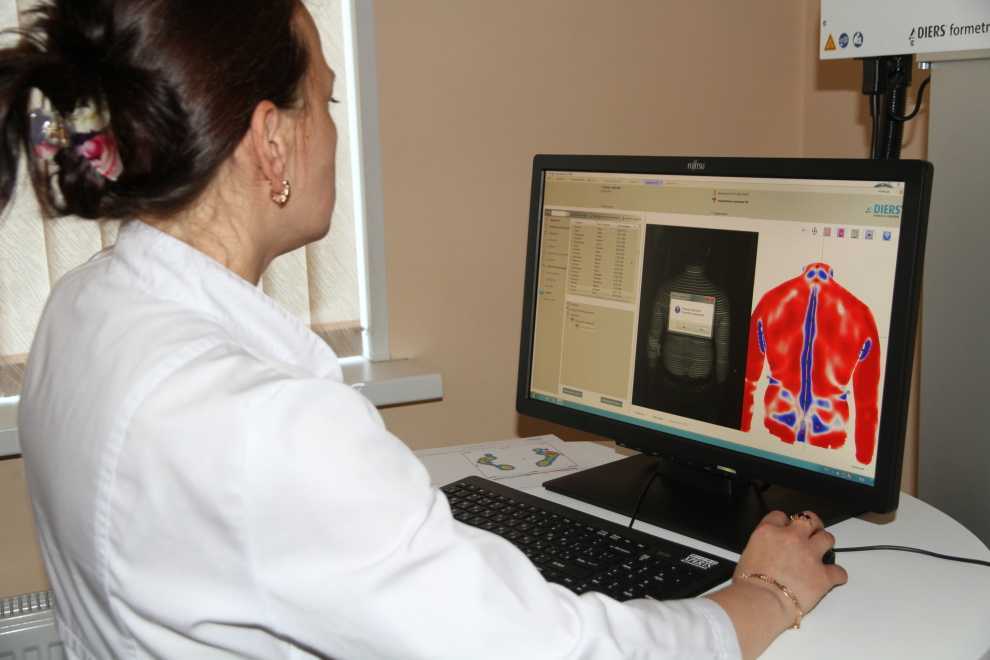

Оптическая диагностика позвоночника Diers: изображения и технологии

Раздел: Мир в картинках